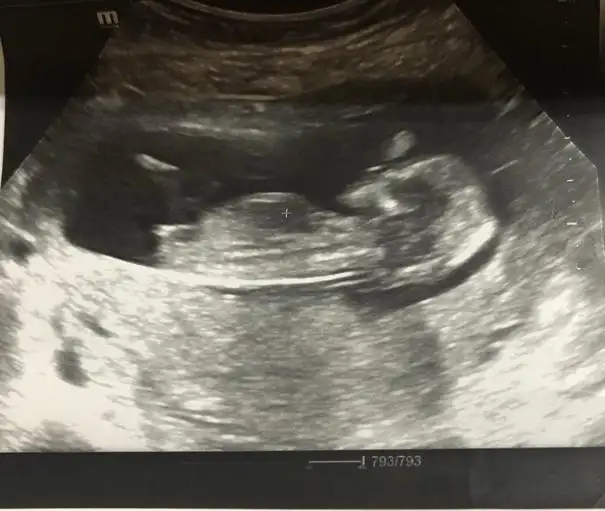

12+5 karindan banada cinsiyet tahmini yaparmsnzbebeğin kız canım nub düz☺

Cnm sanki sırtı dönük gibi başka usg yok mu12+5 karindan banada cinsiyet tahmini yaparmsnz

Kız gibi geldi cnmSizce nedir cinsiyeti?